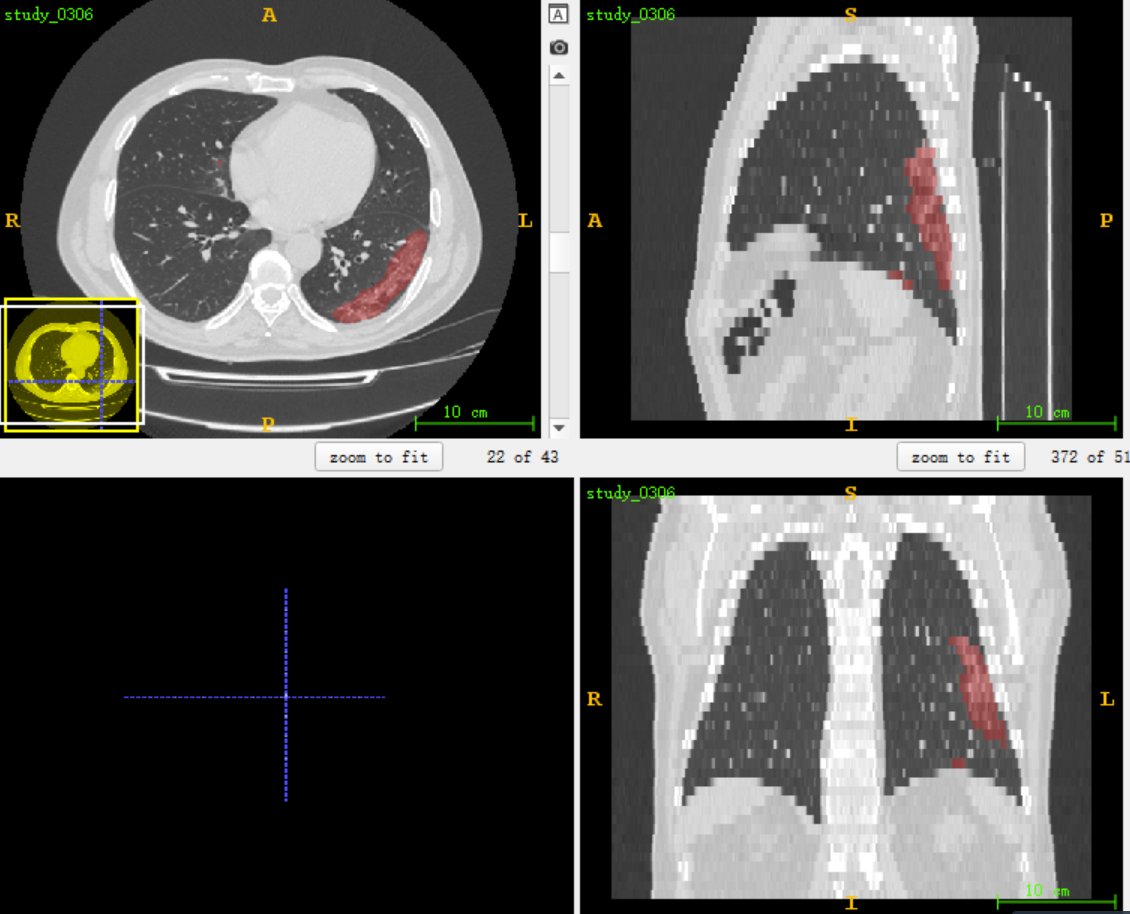

把预测出来的maskNifit格式与原始数据格式,用itk-SNAP叠加读取打开查看